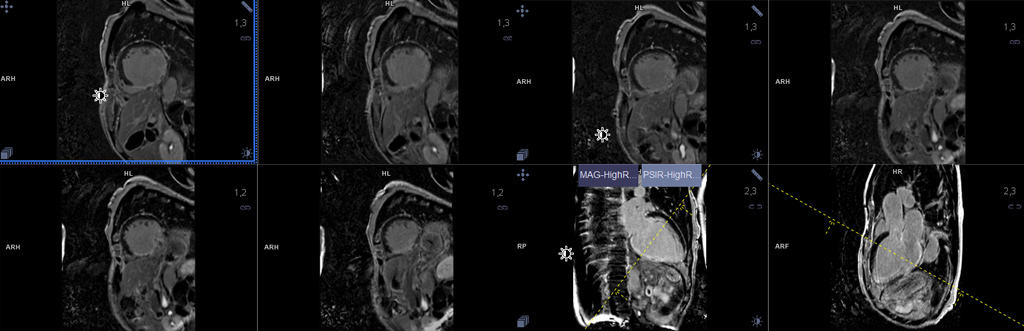

เป็นการใช้เทคโนโลยีขั้นสูงสร้างภาพด้วยสนามแม่เหล็กไฟฟ้าเพื่อตรวจโครงสร้างและการทำงานของหัวใจ อีกทั้งสามารถประเมินการไหลเวียนของเลือดในหัวใจได้อย่างมีประสิทธิภาพ ข้อมูลที่ได้ช่วยในการการวินิจฉัยโรคหัวใจแต่ละชนิดได้อย่างแม่นยำ และสามารถวางแผนการรักษาให้กับคนไข้แต่ละคนอย่างเหมาะสม

จุดเด่นของการตรวจหัวใจด้วยเครื่องสร้างภาพด้วยสนามแม่เหล็กไฟฟ้า (Cardiac MRI) คือความคมชัดของภาพ และประสิทธิภาพในการประเมินการทำงาน รวมทั้งการไหลเวียนเลือดผ่านหัวใจทุกห้องอย่างละเอียด นอกจากนี้ผู้รับการตรวจไม่เจ็บตัว และไม่ต้องนอนโรงพยาบาล